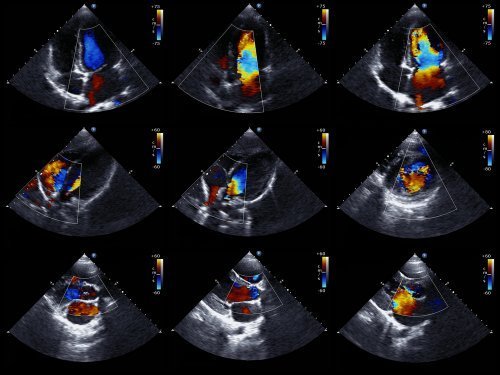

Para uma observação mais exaustiva, o ecocardiograma é uma técnica mais visual do movimento do coração. O ecocardiograma é um exame médico muito utilizado, já que permite obter imagens em movimento do coração. Dessa forma, pode-se avaliar o estado das cavidades cardíacas e seu movimento, e assim confirmar ou descartar a presença de isquemia.

Também se pode avaliar o tamanho do coração, sua força e o estado das paredes que delimitam suas câmaras. Além disso, trata-se de um exame não invasivo, que não traz riscos para o paciente. É assim porque usa ultrassom para conseguir as imagens do órgão.

A ausência de alterações na mobilidade da parede cardíaca exclui a presença de isquemia importante. No entanto, a existência de anormalidades em tal mobilidade não é exclusiva da SCA. Por isso, devem-se avaliar conjuntamente os resultados dos exames e os sintomas.